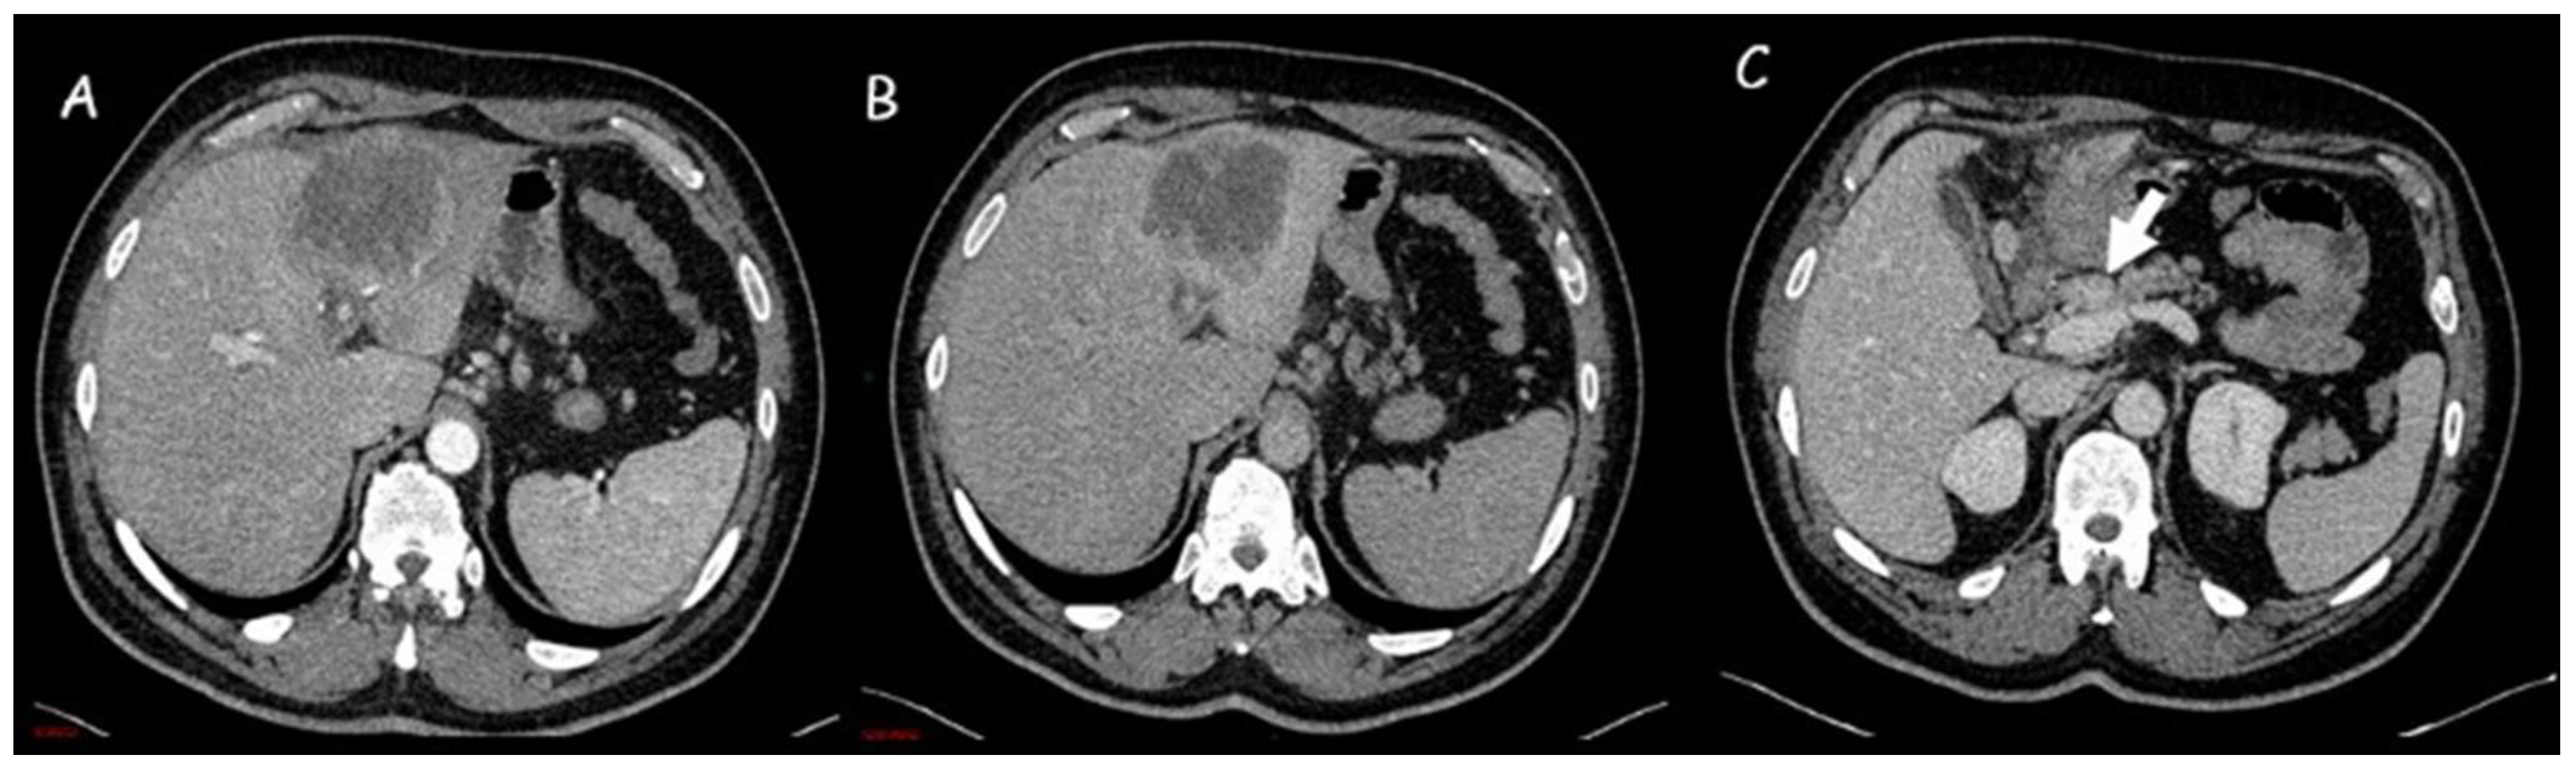

1.1. Computed Tomography

- Kim, S.A.; Lee, J.M.; Lee, K.B.; Kim, S.H.; Yoon, S.H.; Han, J.K.; Choi, B.I. Intrahepatic Mass-forming Cholangiocarcinomas: Enhancement Patterns at Multiphasic CT, with Special Emphasis on Arterial Enhancement Pattern—Correlation with Clinicopathologic Findings. Radiology 2011, 260, 148–157. [Google Scholar] [CrossRef]

- Iavarone, M.; Piscaglia, F.; Vavassori, S.; Galassi, M.; Sangiovanni, A.; Venerandi, L.; Forzenigo, L.V.; Golfieri, R.; Bolondi, L.; Colombo, M. Contrast enhanced CT-scan to diagnose intrahepatic cholangiocarcinoma in patients with cirrhosis. J. Hepatol. 2013, 58, 1188–1193. [Google Scholar] [CrossRef]

- Kim, Y.; Yeom, S.; Shin, H.; Choi, S.H.; Rhee, H.; Park, J.H.; Cho, E.; Park, S.; Lee, S.S.; Park, M. Clinical Staging of Mass-Forming Intrahepatic Cholangiocarcinoma: Computed Tomography Versus Magnetic Resonance Imaging. Hepatol. Commun. 2021, 5, 2009–2018. [Google Scholar] [CrossRef]

- Ciresa, M.; De Gaetano, A.M.; Pompili, M.; Saviano, A.; Infante, A.; Montagna, M.; Guerra, A.; Giuga, M.; Vellone, M.; Ardito, F.; et al. Enhancement patterns of intrahepatic mass-forming cholangiocarcinoma at multiphasic computed tomography and magnetic resonance imaging and correlation with clinicopathologic features. Eur. Rev. Med. Pharmacol. Sci. 2015, 19, 2786–2797. [Google Scholar]